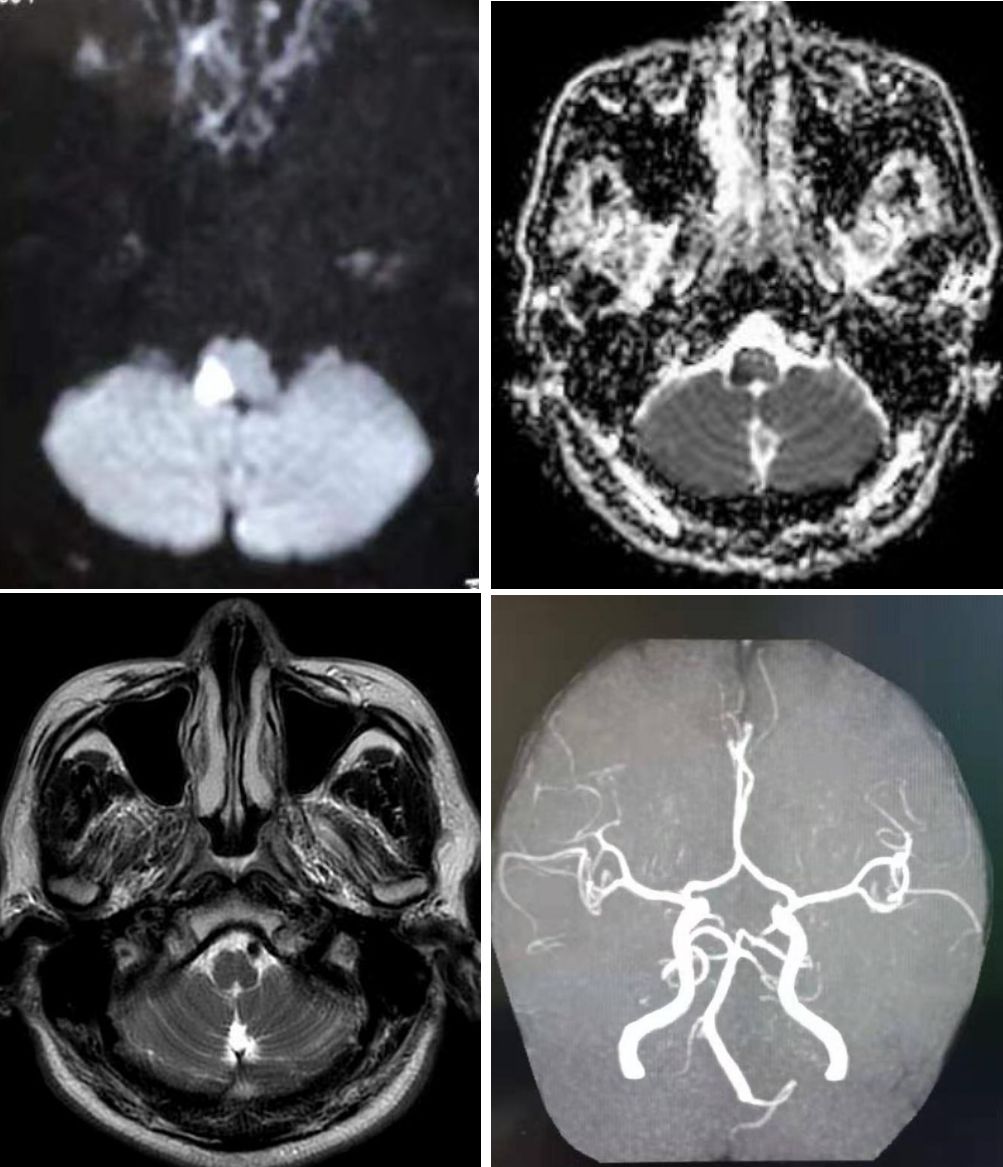

病例2

患者50岁,女,突发构音困难,眩晕、左侧肢体外旋,体检发现双手掌侧小(<1毫米)无痛性皮疹,患者12年前小脑后下动脉区梗死。患者12年前在小脑后下动脉区域有梗塞。既往心脏3.5厘米的粘液瘤术后9年。

答案:长期复发性心脏粘液瘤相关复发性脑梗死。

➤ A:左手掌面Janeway病变。在拇指和手掌的掌侧有数个红色斑皮疹(箭头)。

➤ B:DWI可见双侧小脑均多处弥散受限,多为小脑后下动脉区。

➤ C:患者经食管超声心动图示左心房3.5 cm大小粘液瘤。

Carney综合征是一种罕见的遗传性疾病,最早由J Aidan Carney在1985年首先描述。作为一种罕见的多发性内分泌腺瘤综合征,其特征为皮肤和黏膜表面出现独特的色素沉着、心脏和心脏外出现粘液性肿瘤,以及多发性内分泌肿瘤。多发性内分泌肿瘤、皮肤及心脏累及是本病的基本特点。心脏粘液瘤是猝死的重要原因。其临床表现复杂多样,缺乏特异性,误诊率较高。全身症状主要有嗜睡、疲劳、发热、食欲低下、痛性红斑、体重减轻等。诊断困难时,经食管超声和MRI有一定帮助。